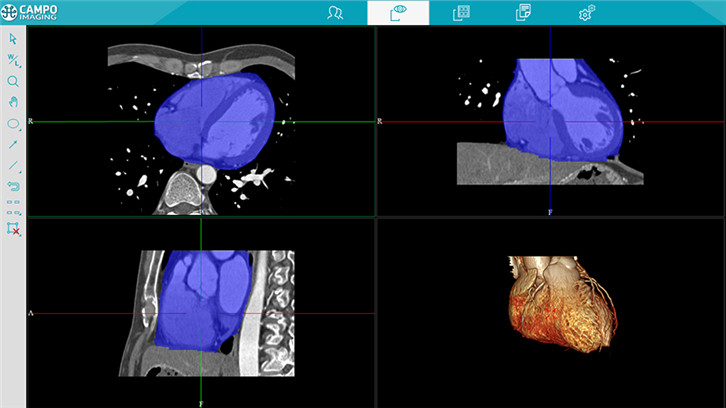

心功能分析

三维图像重建